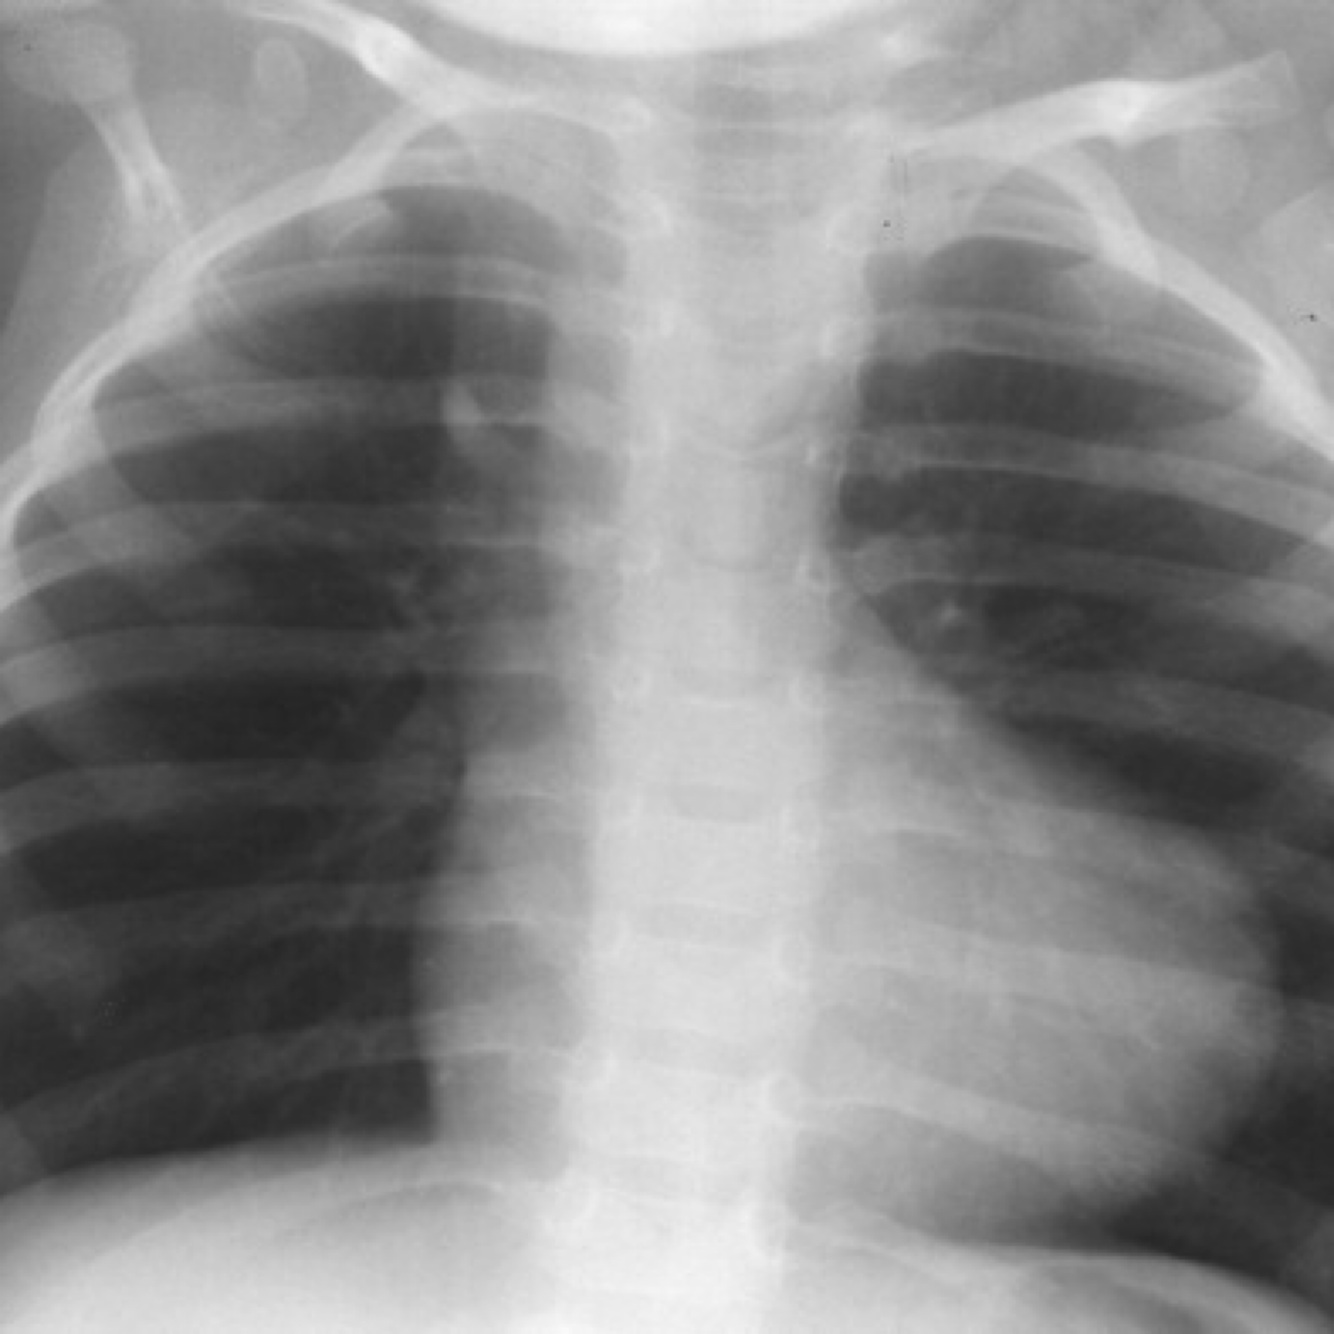

Pulmonary edema